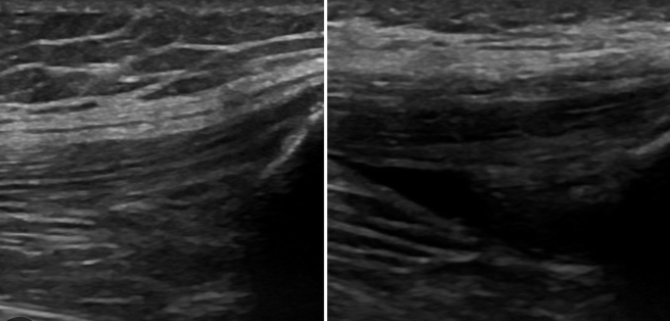

영상검사: 엑스레이, 초음파, MRI 등으로 관절 상태 확인

관절 천자술: 무릎 관절액을 바늘로 뽑아 성분 분석 및 감염 여부 확인